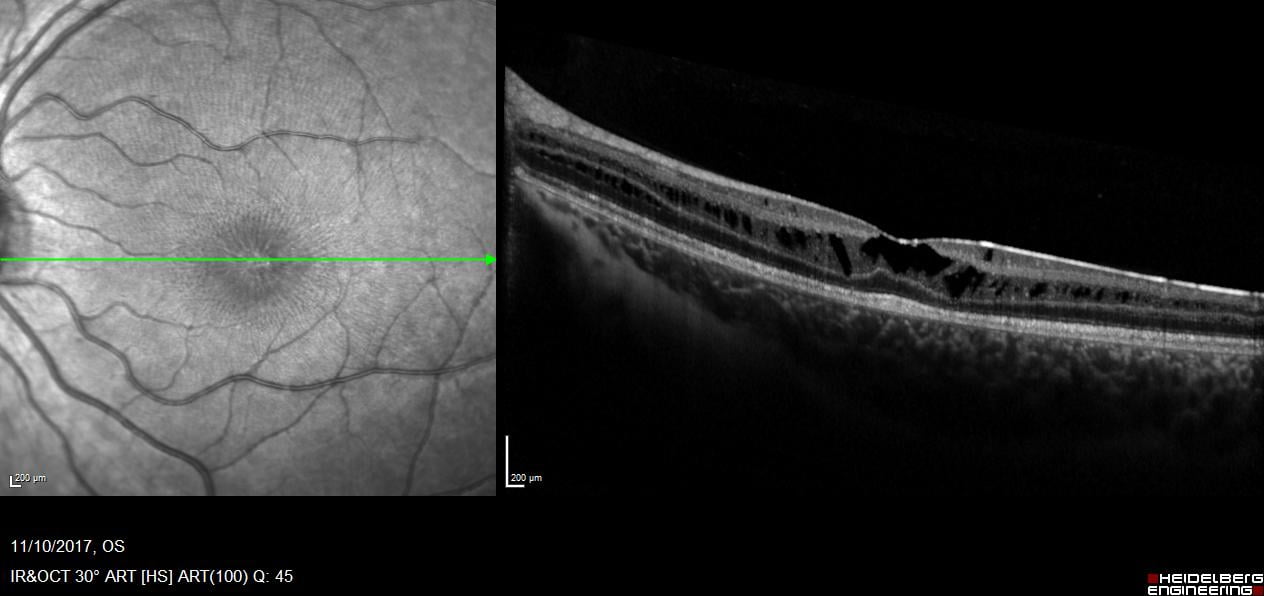

Η συγγενής φυλοσύνδετη ρετινόσχιση είναι μια κληρονομούμενη δυστροφία του αμφιβληστροειδή η οποία οφείλεται σε μεταλλάξεις του γονιδίου RS1. Εμφανίζεται με μείωση της κεντρικής όρασης σε νεαρούς άρρενες. Ο ηλεκτροφυσιολογικός έλεγχος (Ηλεκτροαμφιβληστροειδογράφημα) είναι πολύτιμος για τη διάγνωση της νόσου μιας και έχει χαρακτηριστικά ευρήματα στις καταγραφές ενώ ο γενετικός έλεγχος ταυτοποιεί τη διάγνωση.